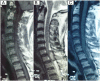

We report a 58-year-old man presenting with acute paraplegia. MRI showed a haematoma within a well-defined epidural lesion at C7-D1. Intraoperatively, organised epidural haematoma surrounded by tumour tissue was found. The final histopathology report was angiolipoma. The patient had dramatic recovery. Angiolipomas should be considered in the differential diagnosis of acute paraplegia when imaging shows well-circumscribed haematoma.